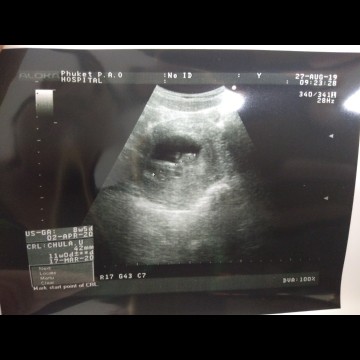

อัลตร้าซาวด์

ที่ภาพไม่ชัดเป็นเพราะเครื่องหรือเพราะอะไรคะ อันนี้ซาวด์เมื่อ2สัปดาห์ที่แล้วค่ะ

อาจจะเปนกับเครื่องหรอไม่ก็หน้าท้องหนาค่ะ